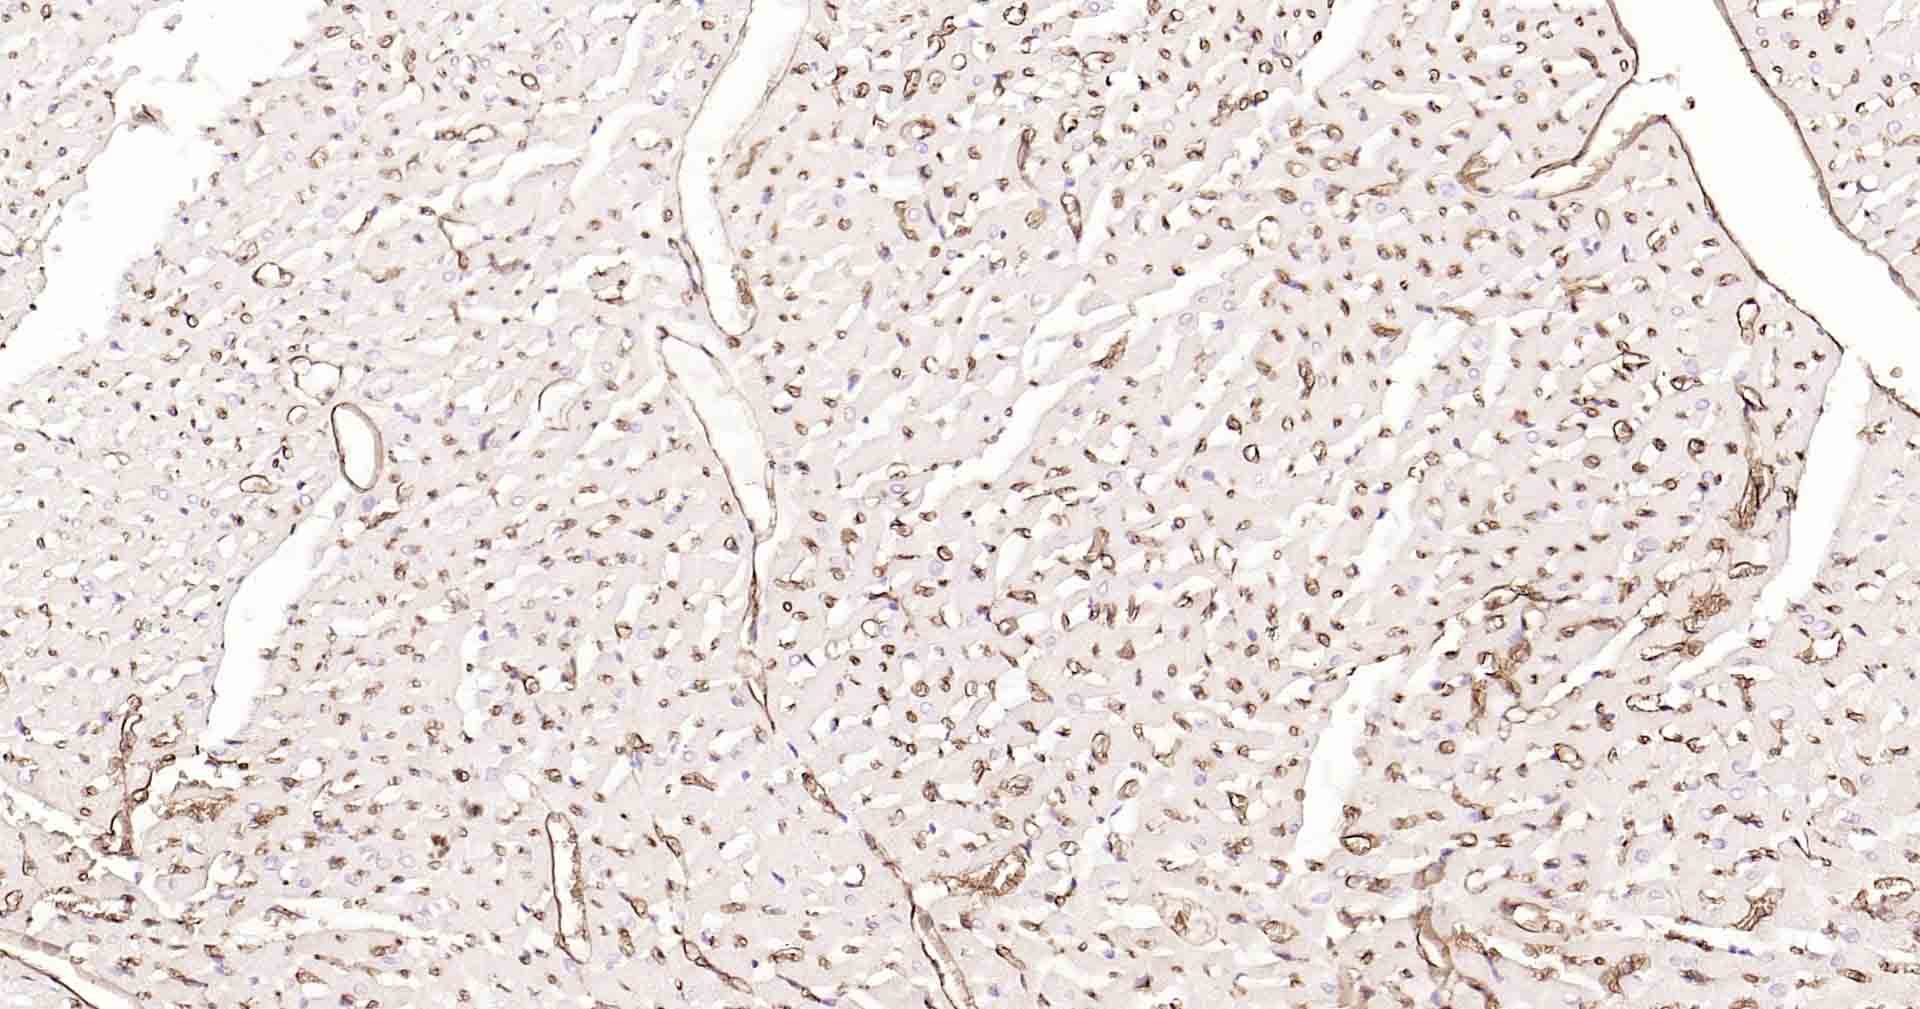

Paraformaldehyde-fixed, paraffin embedded Human Heart; Antigen retrieval by boiling in sodium citrate buffer (pH6.0) for 15 min; Antibody incubation with AQP1 Monoclonal Antibody, Unconjugated(bsm-52909R) at 1:200 overnight at 4°C, followed by conjugation to the SP Kit(Rabbit, SP-0023) and DAB (C-0010) staining.

Paraformaldehyde-fixed, paraffin embedded Rat Heart; Antigen retrieval by boiling in sodium citrate buffer (pH6.0) for 15 min; Antibody incubation with AQP1 Monoclonal Antibody, Unconjugated(bsm-52909R) at 1:200 overnight at 4°C, followed by conjugation to the SP Kit(Rabbit, SP-0023) and DAB (C-0010) staining.

Paraformaldehyde-fixed, paraffin embedded Mouse Heart; Antigen retrieval by boiling in sodium citrate buffer (pH6.0) for 15 min; Antibody incubation with AQP1 Monoclonal Antibody, Unconjugated(bsm-52909R) at 1:200 overnight at 4°C, followed by conjugation to the SP Kit(Rabbit, SP-0023) and DAB (C-0010) staining.